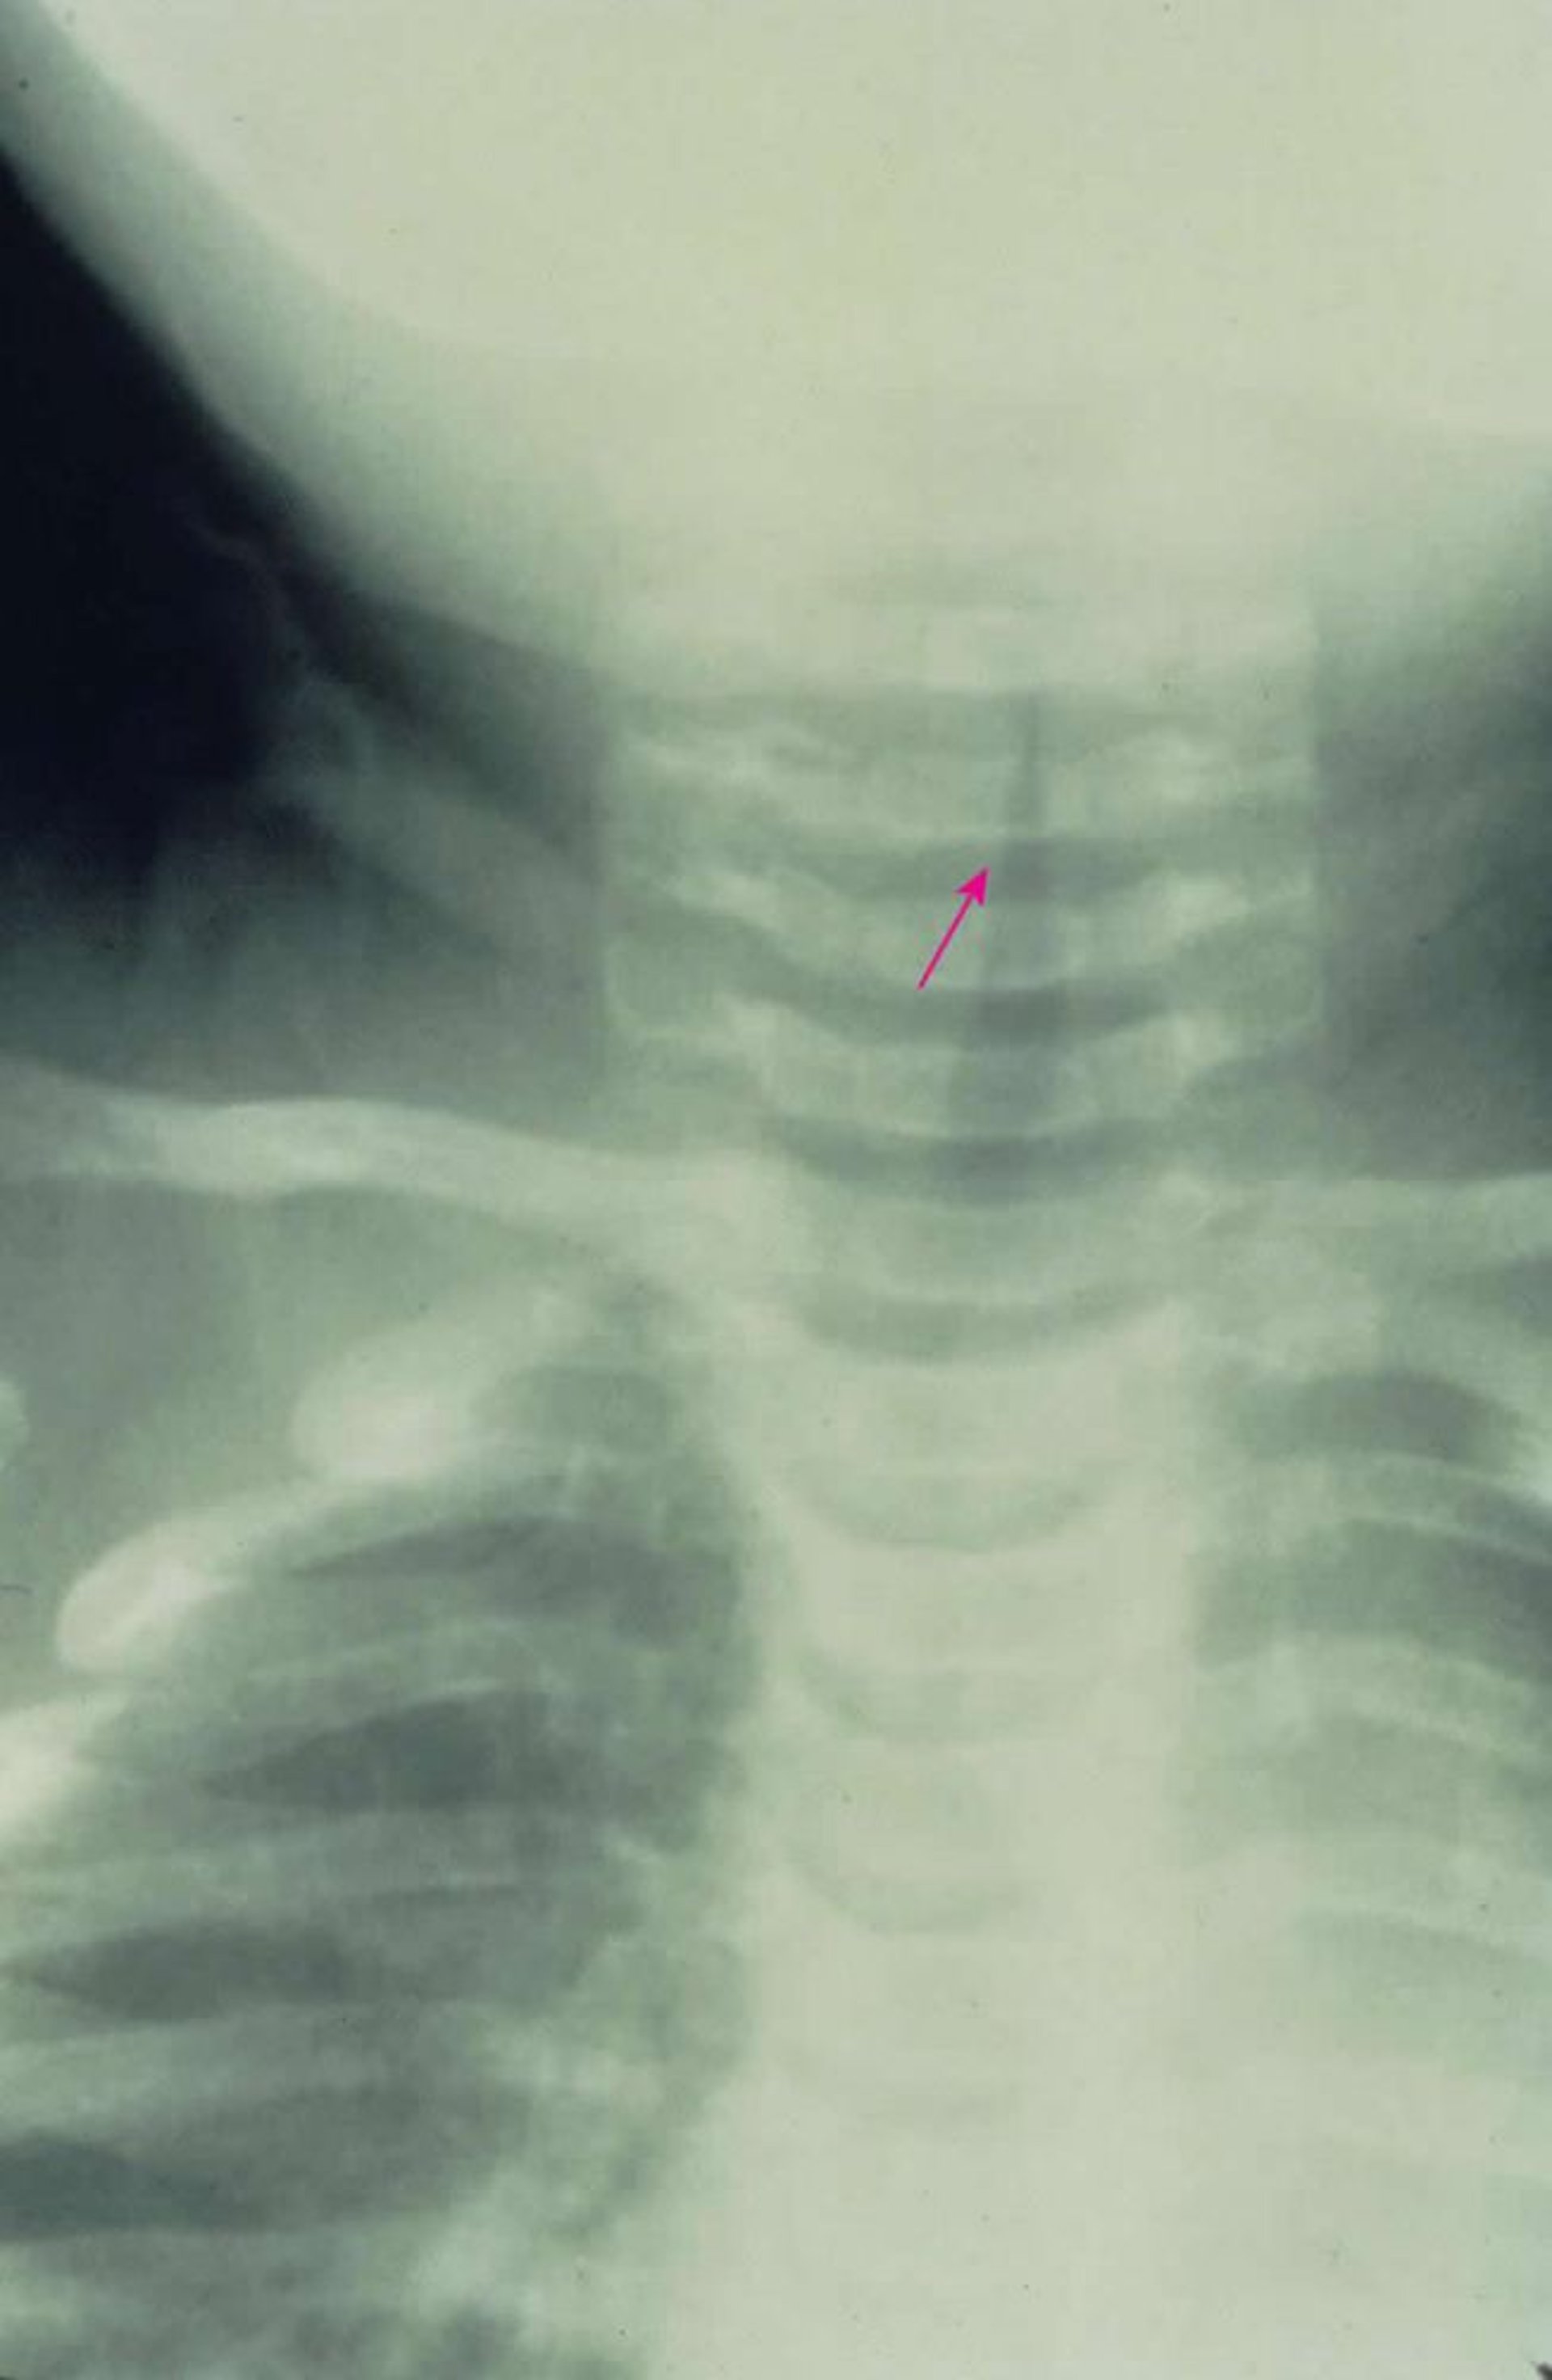

This anterior-posterior x-ray shows characteristic subglottic narrowing of the airway (steeple sign [arrow]) caused by croup.

Image provided by Clarence T. Sasaki, MD.